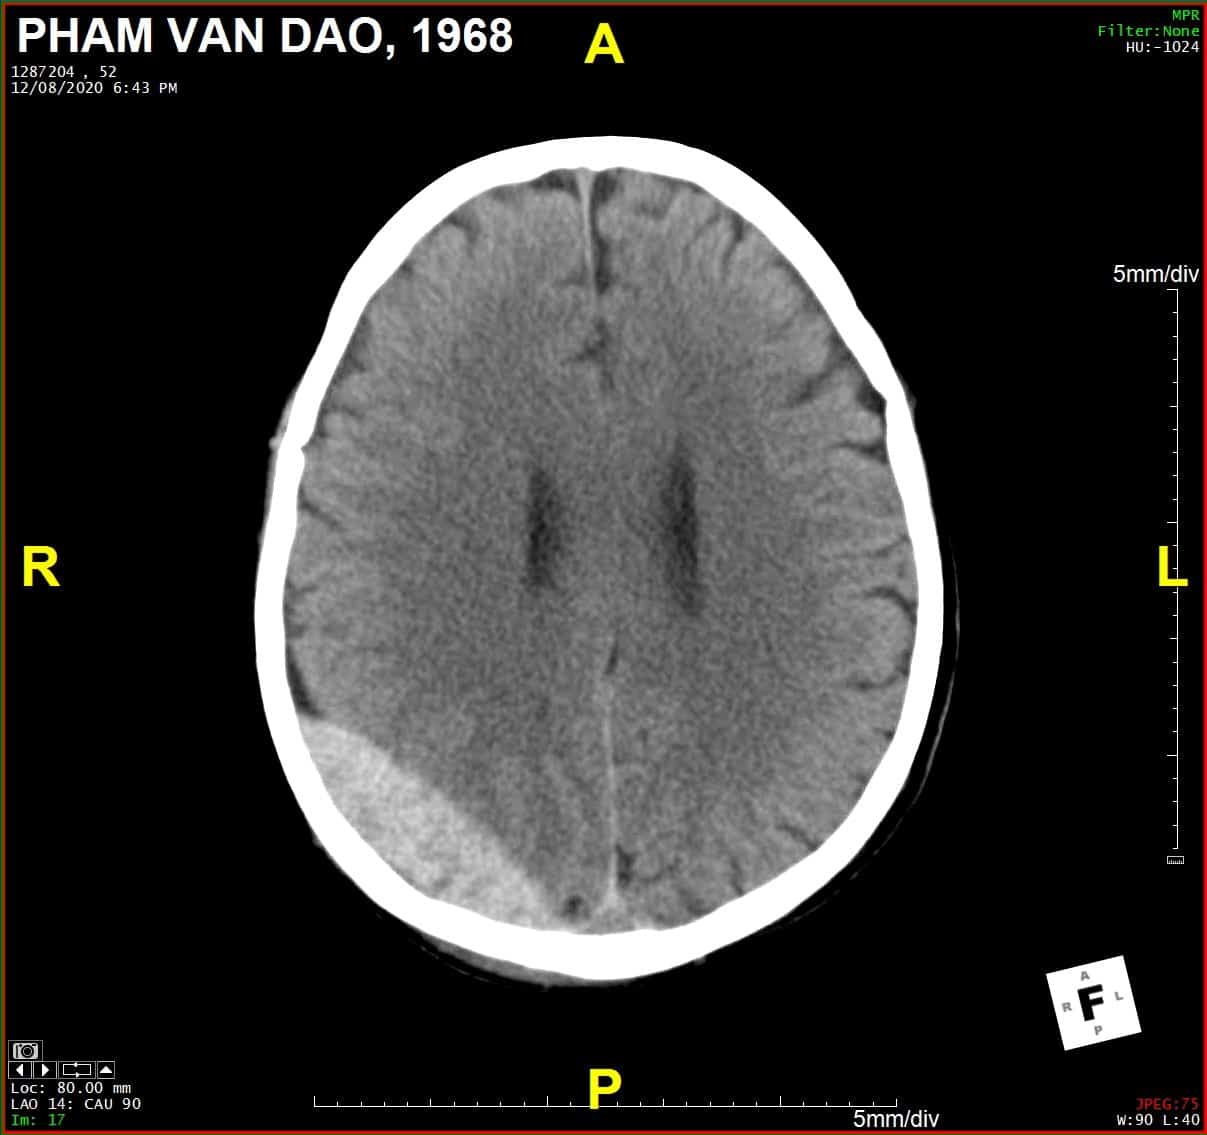

Chấn thương sọ - Ảnh 2

Coronal

» Thông tin: Nam giới – 52 tuổi.

» Lâm sàng: Chấn thương sọ não.

# Tụ máu ngoài màng cứng vùng chẩm phải / Vỡ xương chẩm phải: đường vỡ thẳng (Linear fracture) không thấy rõ trên hướng cắt Axial => quan sát rõ trên hướng cắt Coronal và Sagittal.